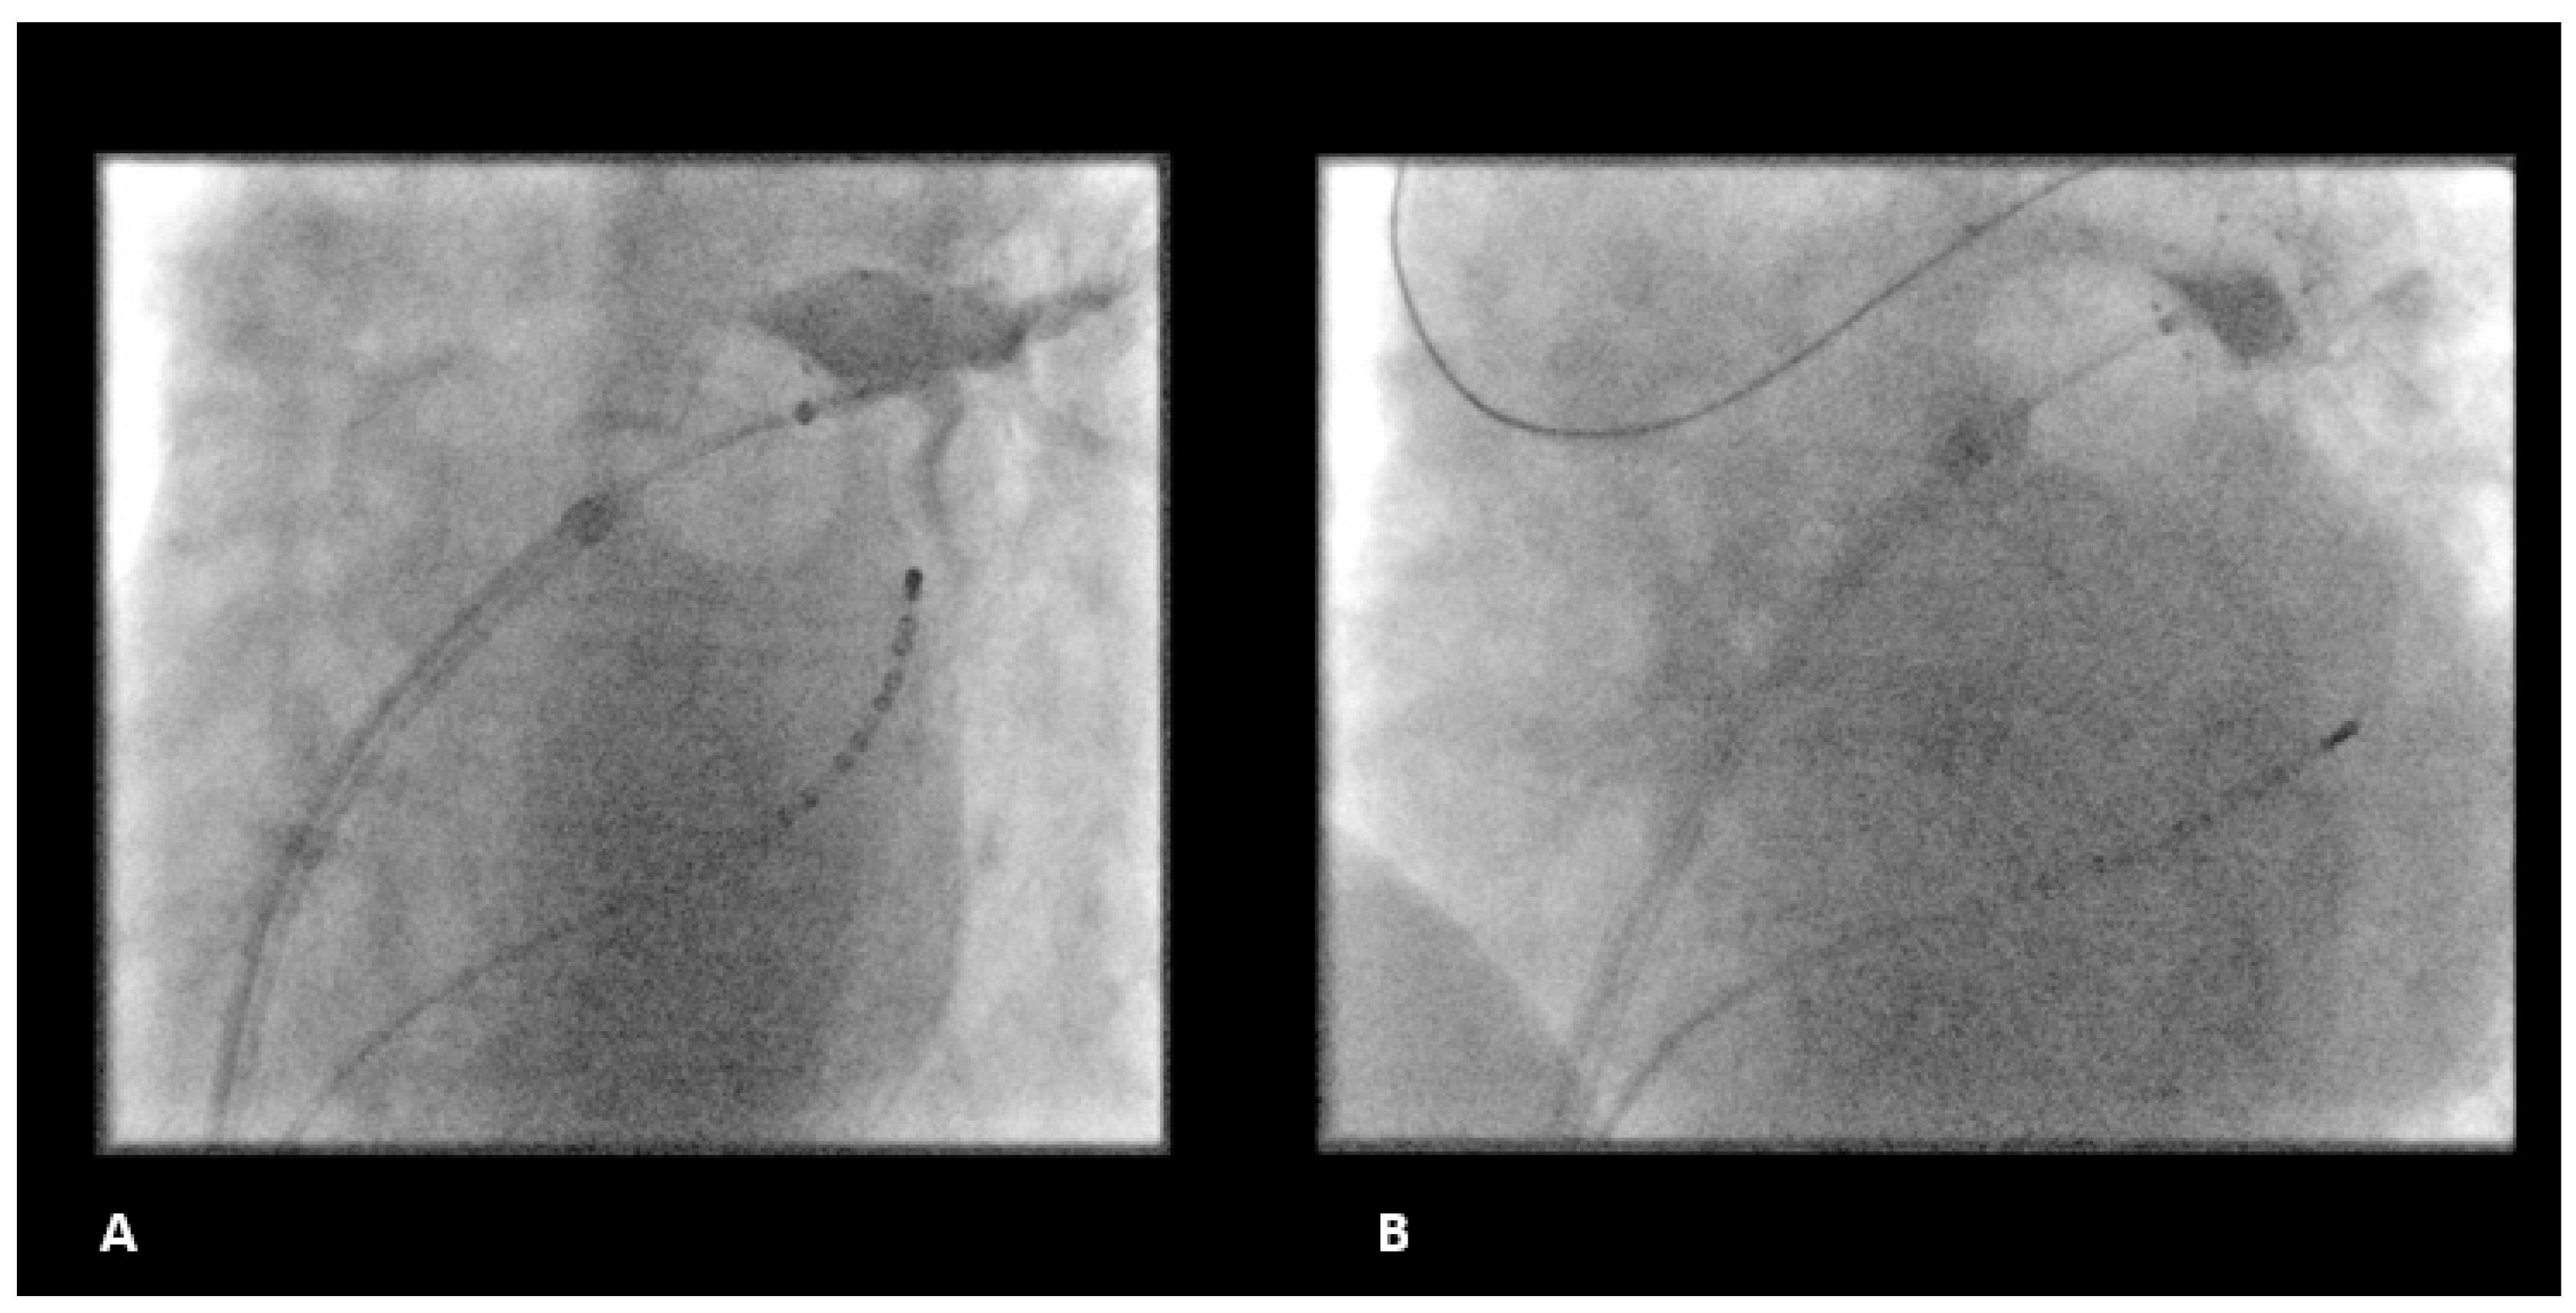

2.2. Ablation Procedure